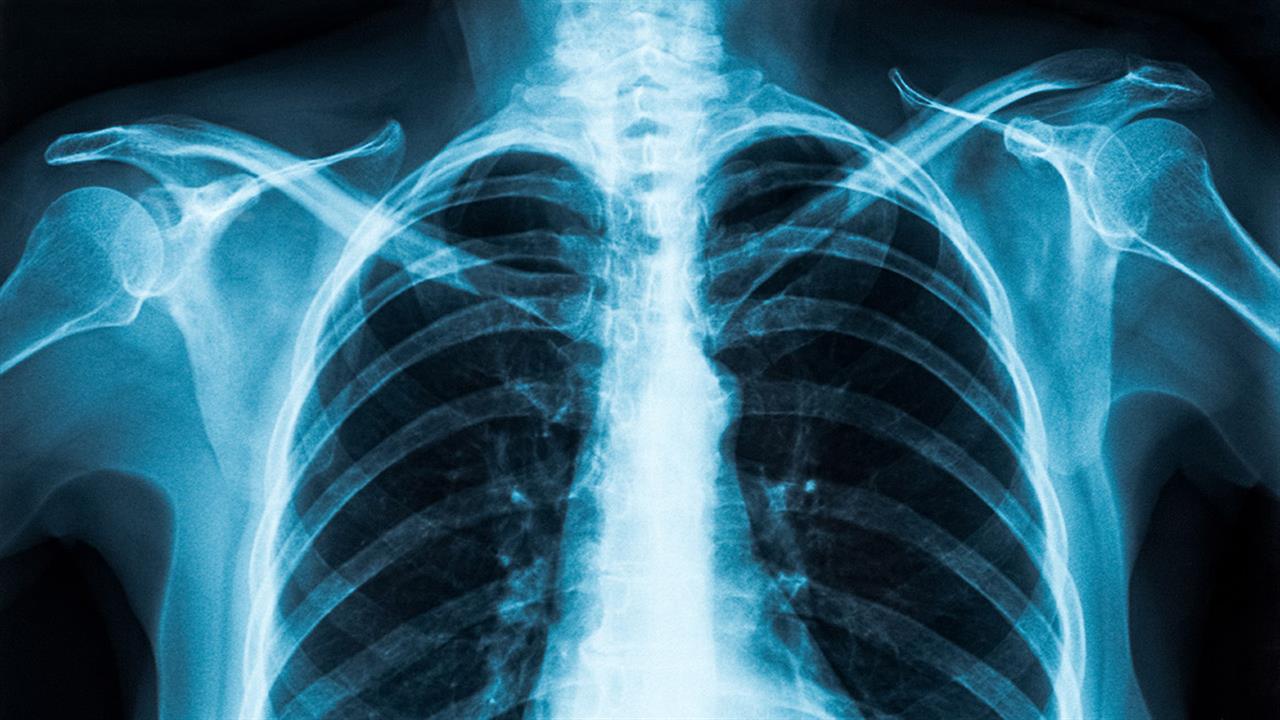

Ερευνητές ανέπτυξαν σύστημα τεχνητής νοημοσύνης που μπορεί να εντοπίσει γρήγορα την COVID-19 από ακτινογραφία θώρακος με ακρίβεια άνω του 98%.

Το νεο σύστημα τεχνητής νοημοσύνης χρησιμοποιεί αλγόριθμο που ονομάζεται Custom Convolutional Neural Network (Custom-CNN) ο οποίος μπορεί γρήγορα και με ακρίβεια να κάνει διαχωρισμό μεταξύ περιστατικών COVID-19, φυσιολογικών περιστατικών και πνευμονίας σε ακτινογραφίες.

Tο νέο σύστημα θα μπορούσε να είναι ιδιαίτερα ωφέλιμο σε χώρες με υψηλά επίπεδα COVID-19 όπου υπάρχει έλλειψη ακτινολόγων. Οι ακτινογραφίες θώρακος είναι φορητές, ευρέως διαθέσιμες και παρέχουν χαμηλότερη έκθεση στην ιονίζουσα ακτινοβολία έναντι των αξονικών τομογραφιών.